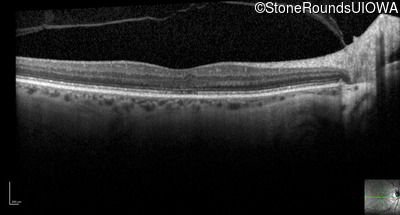

Optical Coherence Tomography - Left - 20/125

Exemplar / OCT Stack

OCT Stack